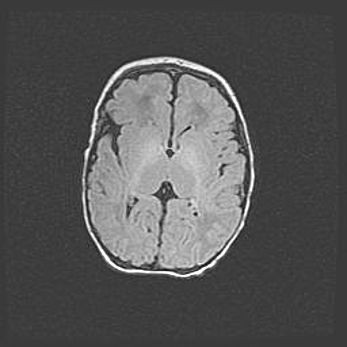

Церебральная ишемия II.

Возраст: 5 дней

Вес: 3400 г

Пол: женский

Окружность головы: 35 см

Срок гестации: 39 недель

Церебральная ишемия – это заболевание, характеризующееся недостаточностью (гипоксией) либо полным прекращением (аноксией) снабжения мозга кислородом по причине закупорки одного или нескольких сосудов. Это приводит к  что метаболическим расстройствам различной степени тяжести в тканях головного мозга, развитию коагуляционных некрозов и гибели нейронов.